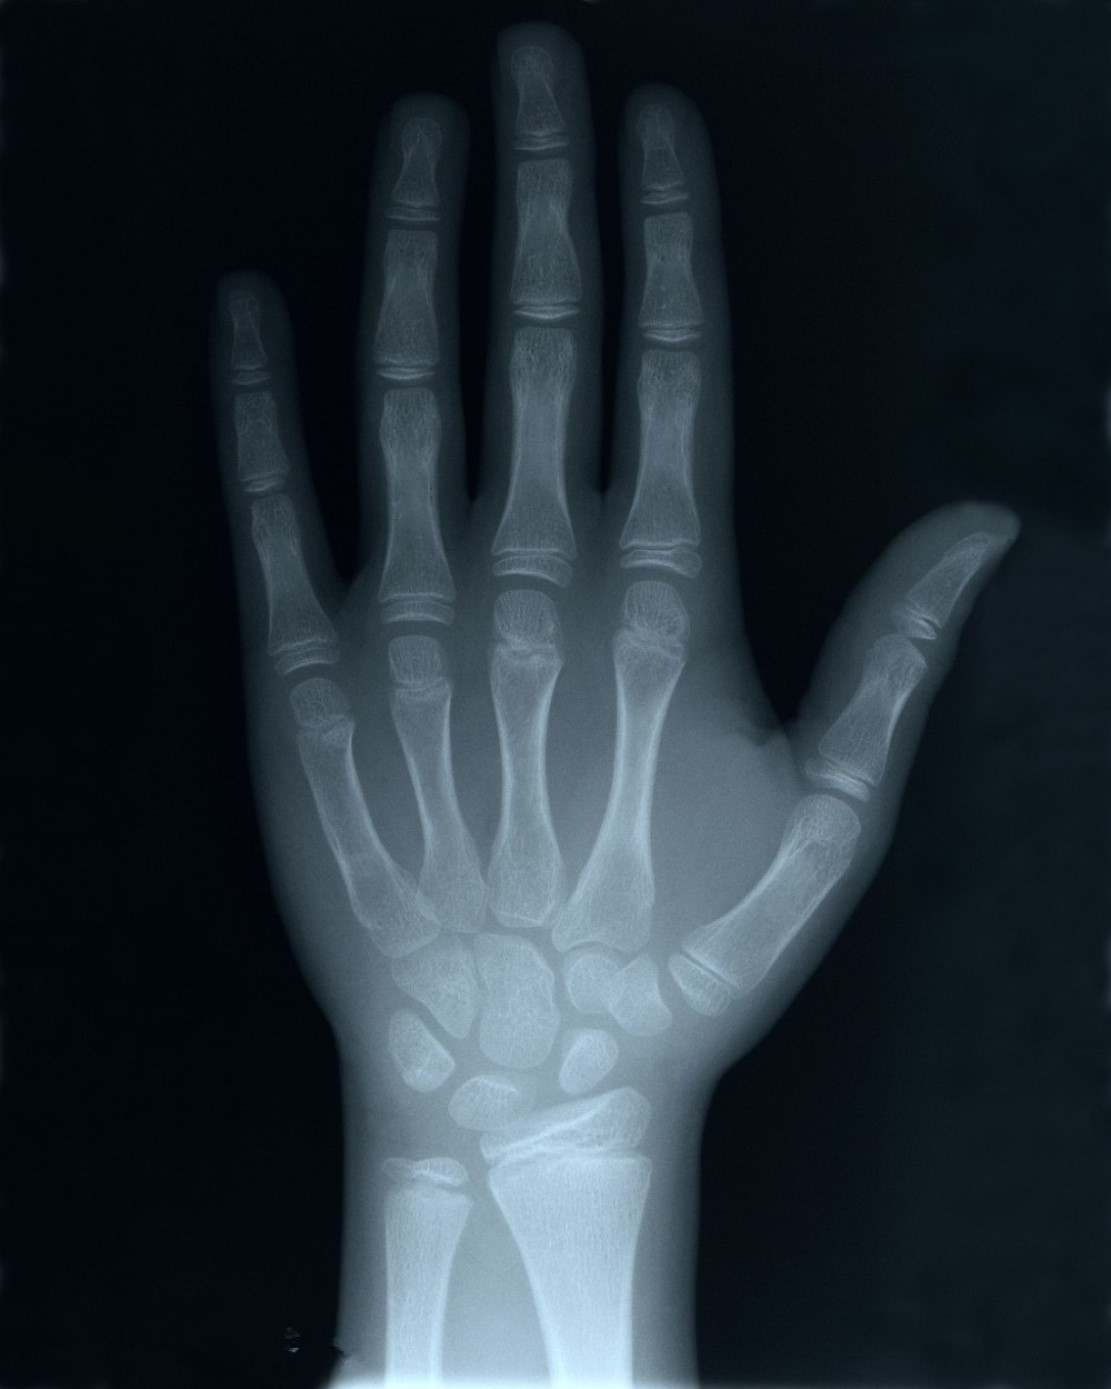

人们到医院做透视和CT检查,就是采用X射线照射,又叫X光。X射线其实就是一种光,但这种光与我们平时了解的光不同,它可以透过人体后某些物体,但眼睛却看不见。

X射线是仅次于γ射线的电磁波,波长在10纳米~0.01纳米之间,频率在3^16~3^20赫兹之间,能量为124eV~1.24MeV。这是每一个光子的能量,属于高能射线,因此穿透力很强。当X光照射人体时,一部分被人体物质吸收,大部分会从原子隙缝穿越透过。

频率越高波长越短的X光能量越大,穿透能力越强。在穿透物体的过程中,根据物体的密度和厚度,吸收不一样,因此穿越的X光就有强有弱,这样就在感光胶片中显示出被穿越物体的结构来。

当他觉得这种新发现的光已经确信无疑,已经过去了7个星期了。1895年12月22日晚上,他说服了自己的夫人来当实验对象,当他夫人将自己带有戒指地伸向荧光屏时,令人震惊而奇异的现象出现了,伦琴夫人看到一只瘦骨嶙峋的手,再仔细一看,那不是手,而是一个个骨节。

夫人不敢相信,这就是自己的手?但在影子的无名指骨节上,分明有一个戒指,与自己戒指戴的位置一点都没有偏差!伦琴夫人被自己的手吓住了,要知道那个年代还有谁看到过这种影像?只有死人的白骨才会这样。

而这是人类第一张X光照得的人体照片!伦琴异常激动地拥抱了夫人。终于证实了,这是一种前所未有的光,能够穿透肉体的光。

伦琴是个低调的人,但1896年1月23日,他在自己的研究所举行了他一生唯一一次报告会,公布了自己的发现。报告会上,伦琴请求维尔茨堡大学著名解剖学家克里克尔,伸出自己的手让他当场用X射线拍摄,克里克尔欣然同意。当拍好的干板经过显影,出现一位八十岁老人优美的手骨时,全场掌声雷动,爆发出欢呼。

最早开发出X光引用的是医学,这就是透视技术。人们通过X光照射,可以看到本应通过解剖才能看到的病变,为无数人更好地解除了病痛。当时英国著名外科医生托马斯·亨利将X射线称为“诊断史上的一个最大的里程碑”。